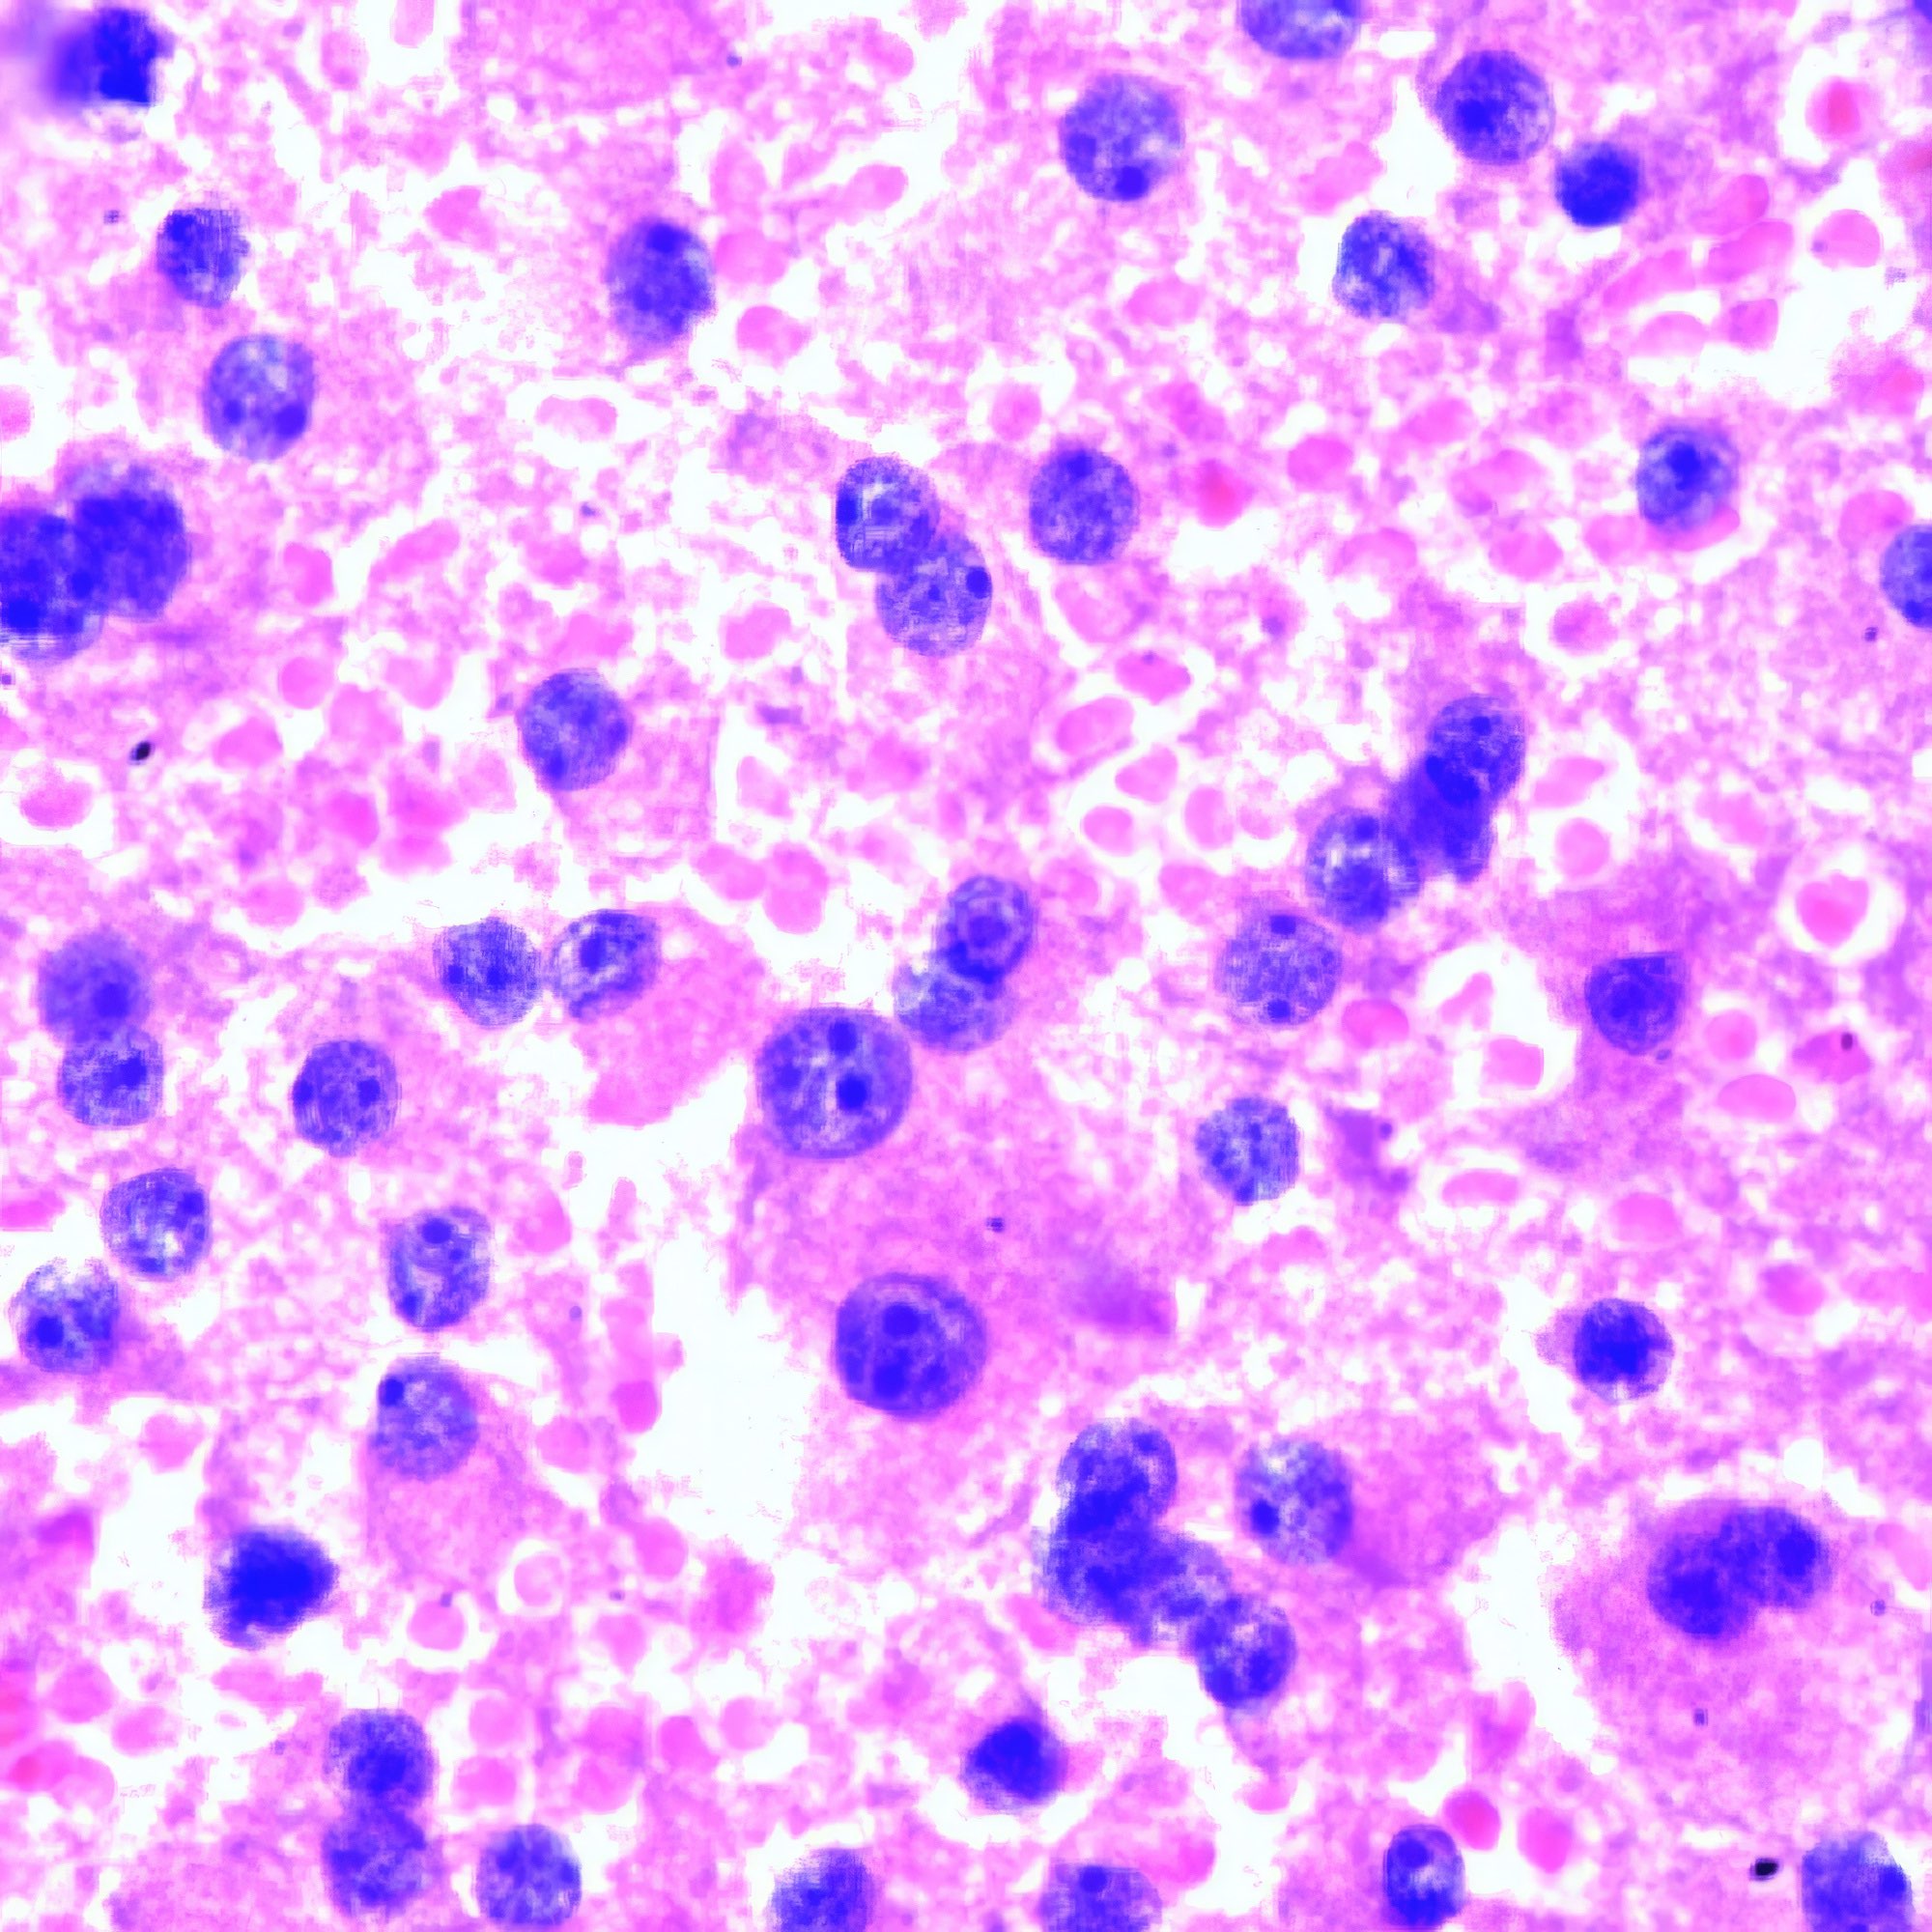

Klinische Angaben

M, 8 Jahre alt, beidseitige Schwellung der Halslymphknoten, weiße Blutzellen 110’000, Lym 43.8%, Gran 23.5%, RBC 2.46, HB 8g/dl, PLT 30 000, CRP 96.

Beschreibung

Die Bilder der Lymphknoten-FNA zeigen außer Blut nur kleine lymphozytäre, keine größeren follikuläre Zellen, wie bei einem Patienten in so jungem Alter zu erwarten. Die kleinen Zellen variieren erheblich in der Form und wenig in der Größe; einzelne von ihnen sind hantelförmig. Vereinzelt geschrumpfte strukturlose pyknotische Kerne (Abb. a li. oben). Die vitalen Zellen zeigen jedoch eine mehr oder weniger normale klumpige Chromatinstruktur (Abb. a, b). Infolge der Trocknung vor der Fixierung erscheinen die Giemsa-gefärbten Zellen im Blutausstrich viel größer, aber auch deutlicher polymorph (Abb. c, d).

Kommentar

Bis vor einigen Jahren wurde die FNA ausschließlich bei erwachsenen Patienten und nur selten bei Kindern angewendet {1}. Im vorliegenden Fall zeigen die ausgezeichneten Bilder, dass das Ergebnis von der Erfahrung des Arztes abhängt, der sie anwendet. Die durch die Pap-Färbung gut sichtbare Chromatinstruktur macht zusätzliche Tests zur Abgrenzung von anderen kleinzelligen Tumoren wie Ewing-Sarkom, Neuroblastom und Wilms-Tumor überflüssig. Die zytologische Diagnose wird durch die klinischen Daten gestützt. Die für die ALL typische Knochenmarksbeteiligung lässt sich an den klinischen Daten ablesen, d.h. an der niedrigen Zahl der roten Blutkörperchen (RBC) und der Blutplättchen sowie dem niedrigen Hämoglobinspiegel (HB). Etwa 80 % der ALL sind vom B-Zell-Typ. Ihre Entwicklung scheint von angeborenen DNA-Veränderungen abzuhängen. Wie in einer neueren Arbeit gezeigt wurde, sind Kinder mit Trisomie 21, der genetischen Ursache des Down-Syndroms, mit einem 20-fach erhöhten Risiko für ALL assoziiert {2}. Im Gegensatz zur ALL tritt die akute myeloische Leukämie (AML) nicht vor der Adoleszenz auf.